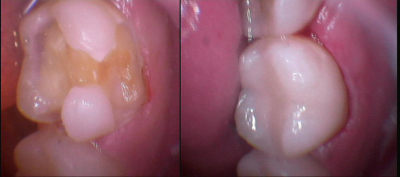

Gallery

Galeria